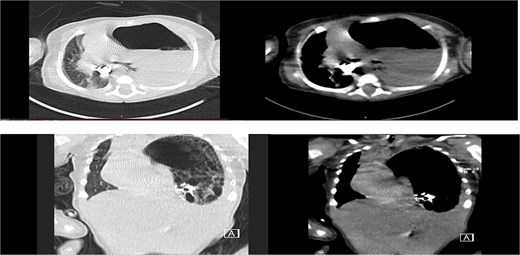

Chest radiograph showed an opaque left hemithorax with mediastinal shift to the right and a large air-fluid level, raising suspicion for diaphragmatic hernia with gastric herniation (Fig. 1a). Abdominal ultrasound revealed a cystic structure in the left thorax consistent with the stomach (Fig. 1b). Computed tomography confirmed a left posterolateral diaphragmatic defect with herniation of the stomach into the thorax, consistent with Bochdalek hernia and tension gastrothorax (Fig. 2).

Axial, coronal CT chest revealed: Left diaphragmatic hernia (Bochdalek hernia) stomach herniation to the left hemithorax with a shift in the mediastinum.